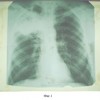

Фиг.3. Больной К-в. Правая боковая проекция после лечения.

10 апреля 2006 г. больному выполнена операция Верхняя лобэктомия справа (фиг.3). Послеоперационный период протекал без осложнений. Швы сняты на 13-14 сутки. Заживление первичное. Г.а. №859952-61 от 13.04.06 г. В ткани легкого и лимфоузлах множественные эпителиоидноклеточные гранулемы с тотальным некрозом, наличием одиночных клеток типа Пирогова, в окружающей легочной ткани пневмосклероз, хроническое воспаление – продуктивная форма туберкулеза (см. фиг.5. Больной К-в. Компьютерная томограмма после проведения трех курсов АГХТ).